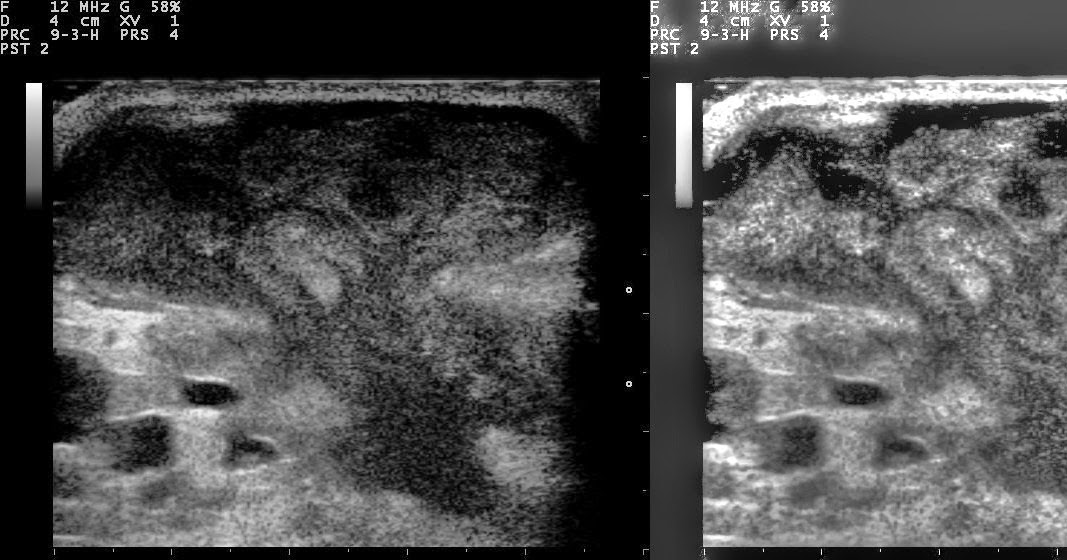

Nevit's blog Ultrasound image of breast abscess. Original version and Abscess Under Breast Treatment for a breast abscess involves antibiotics or a procedure to drain the fluid. It mainly affects women who are. a breast abscess is a localized collection of pus within the breast. suspect a breast abscess if the woman has: Fever and/or general malaise —. Doctors usually drain (aspirate) an abscess with a needle. If your breast infection. Abscess Under Breast.